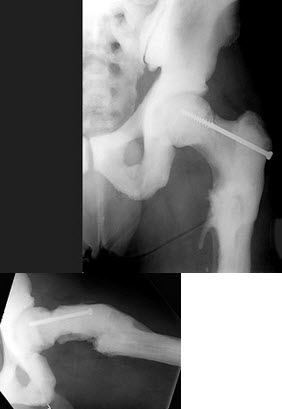

男,根据其正常骨盆影像图像,判断其最可能的年龄()

A.5岁左右

B.10岁左右

C.15左右

D.20岁左右

E.25岁左右

102、单项选择题

女,27岁,双侧髋部疼痛,肿胀2月余,有髋部外伤史,结合图像,最可能的诊断是()

A.股骨颈骨折

B.股骨头骨折

C.慢性骨髓炎

D.慢性骨脓肿

E.骨结核